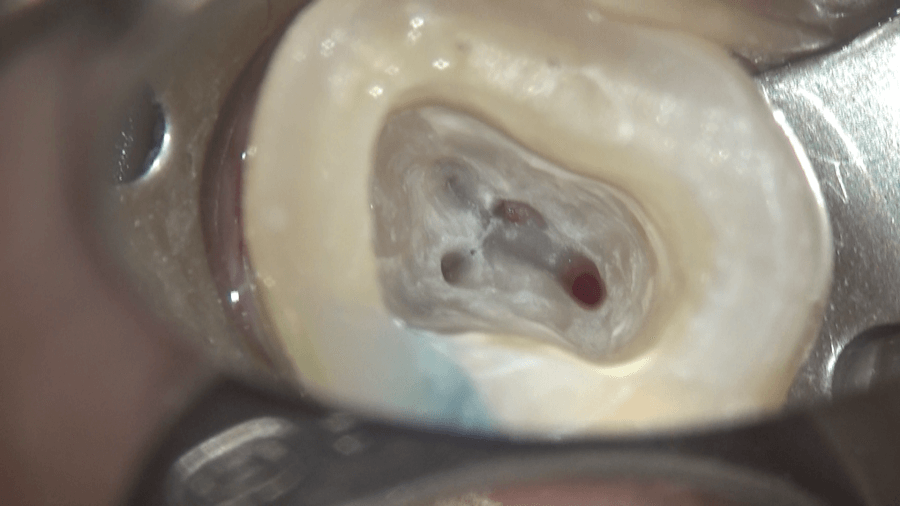

内部にあるゼリー状の組織、歯髄が見えます。これがいわゆる神経です。

もう少し大きくすると、内部に石のようなものが確認できます。

触ると動きます。

上部の歯髄を溶かすと、4つの根管の入り口が見えます。